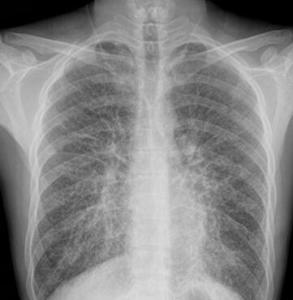

肺泡微结石病(pulmonary alveolar microlithiasis,PAM),是一种少见的疾病,肺泡内存在弥漫分布的含钙,磷盐为主的微小结石。